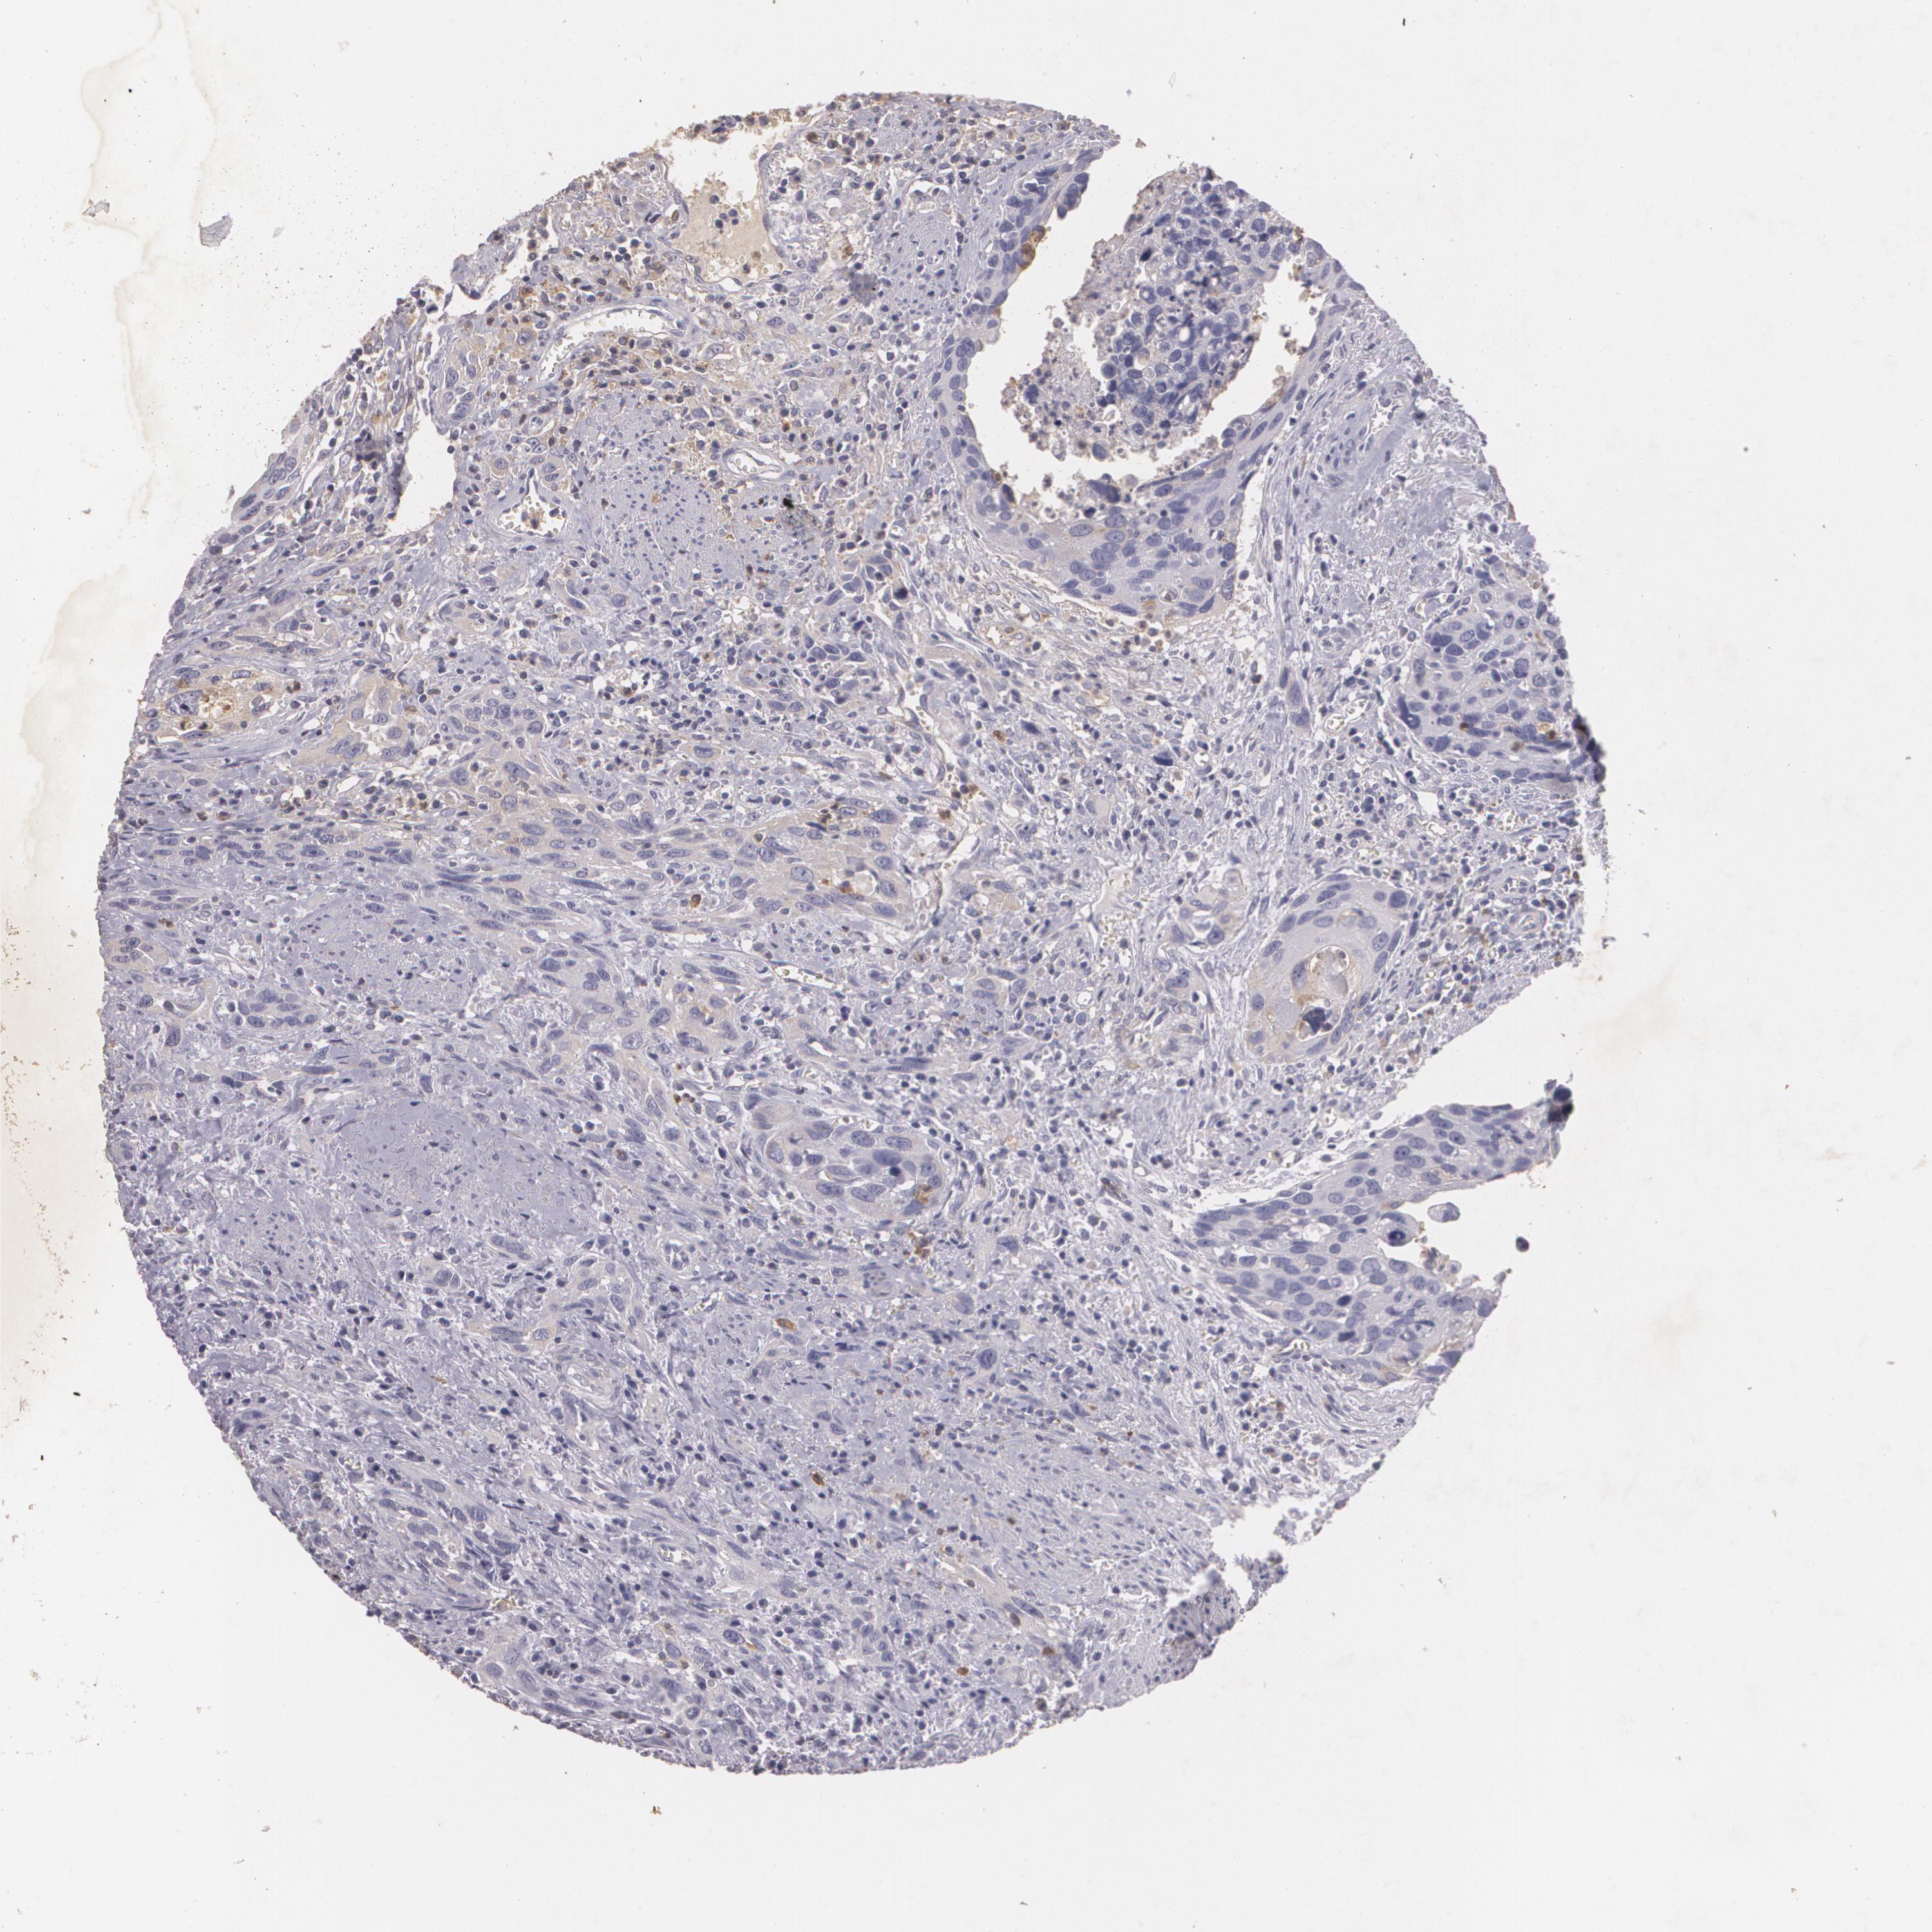

UROTHELIAL CANCER - Protein expressioni

A mouse-over function shows sample information and annotation data. Click on an image to view it in a full screen mode. Samples can be filtered based on level of antibody staining by selecting one or several of the following categories: high, medium, low and not detected. The assay and annotation is described here.

Note that samples used for immunohistochemistry by the Human Protein Atlas do not correspond to samples in the TCGA dataset.

Antibody stainingi

Antibody staining in the annotated cell types in the current human tissue is reported as not detected, low, medium, or high, based on conventional immunohistochemistry profiling in selected tissues. This score is based on the combination of the staining intensity and fraction of stained cells.

Each image is clickable and will lead to virtual microscopy that enables deeper exploration of all samples and also displays staining intensity scores, fraction scores and subcellular localization as well as patient and tissue information for each sample.

Antibody HPA016422

Antibody CAB001977

Staining

High

Medium

Low

Not detected

Intensity

Strong

Moderate

Weak

Negative

Quantity

>75%

75%-25%

<25%

None

Location

Nuclear

Cytoplasmic/membranous

Cytoplasmic/membranous,nuclear

Urothelial carcinoma, Low grade

Urothelial carcinoma, High grade

Adenocarcinoma, NOS